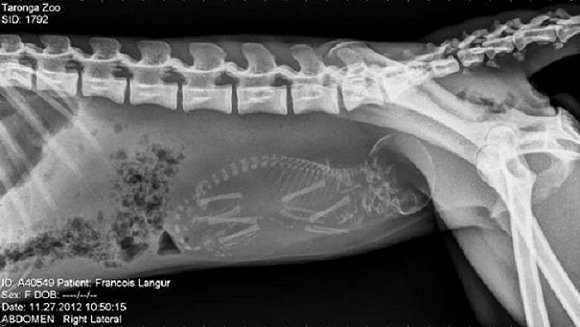

可爱又毛骨悚然 怀孕动物的X光片

人类之间分享母亲肚子里胎儿的X光片是一件非常常见的事情,但是,纵使你觉得自己对X光片已经见怪不怪,在看到了下面这些怀孕动物的X光片后你仍旧会说"哦我的天哪"。

以下就是一些动物在怀孕时的X光片。

2. 黑叶猴